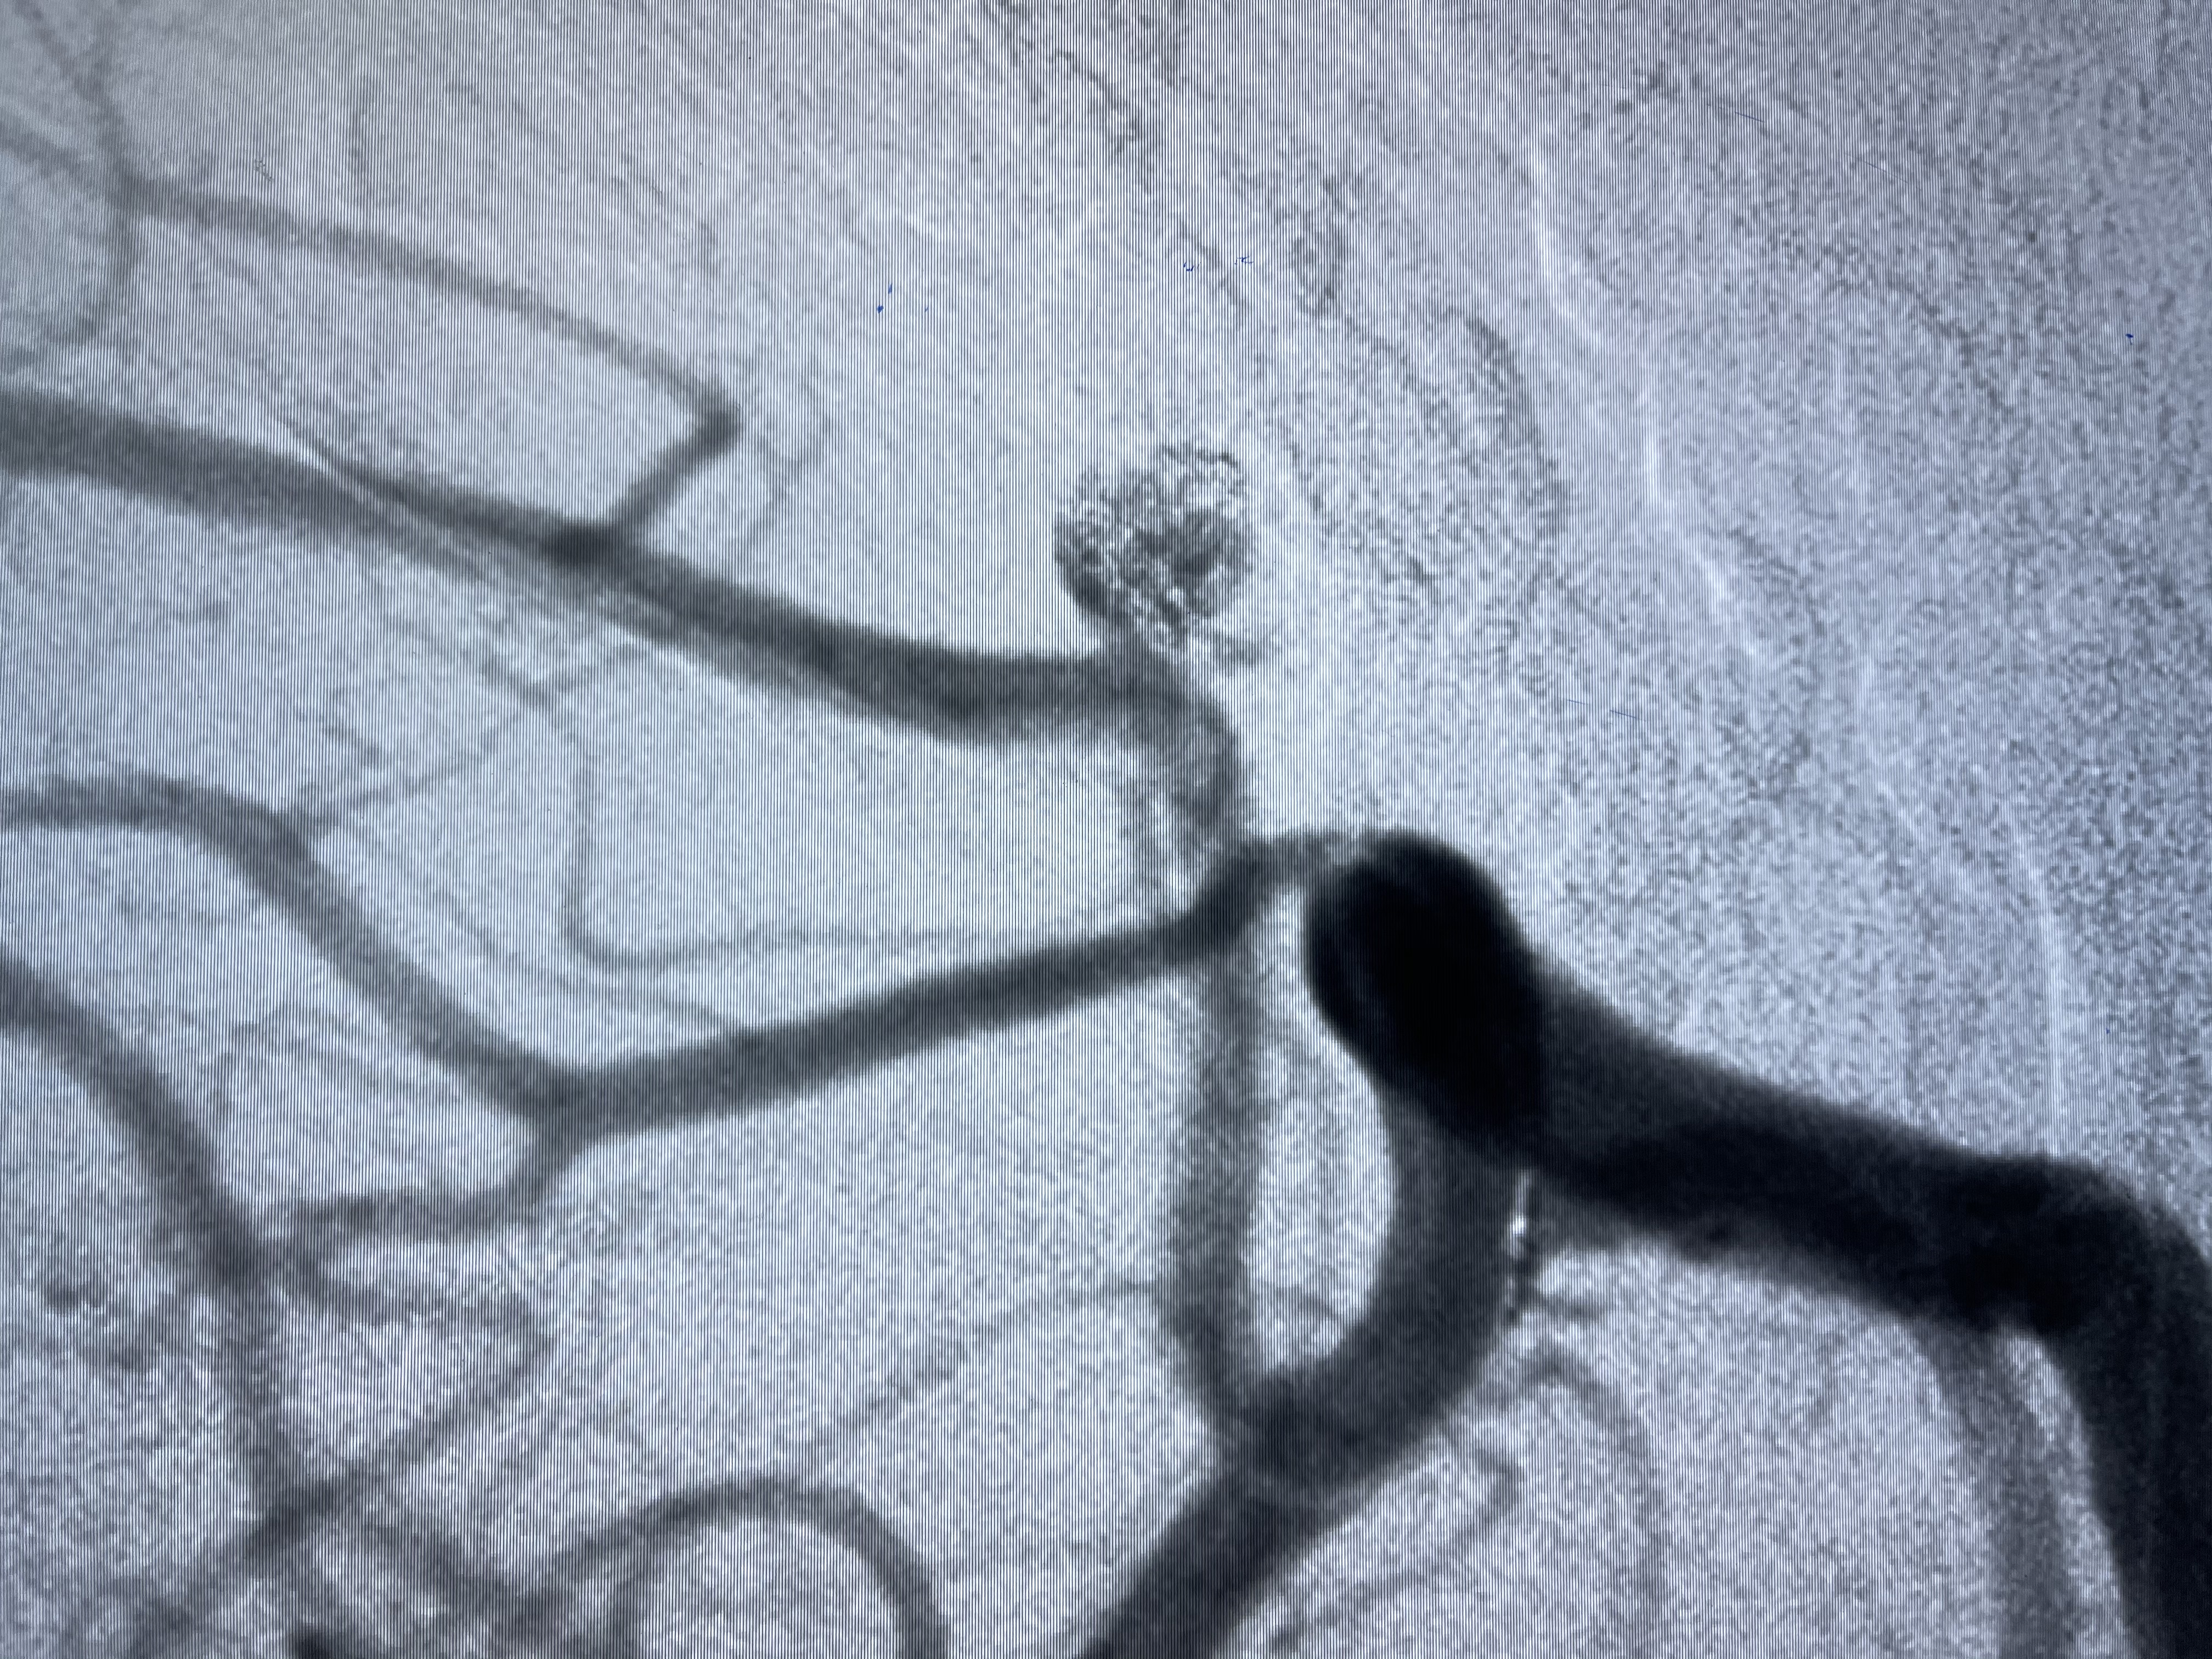

工作角度显示瘤颈

E10 45°角微导管塑形后轻松到位